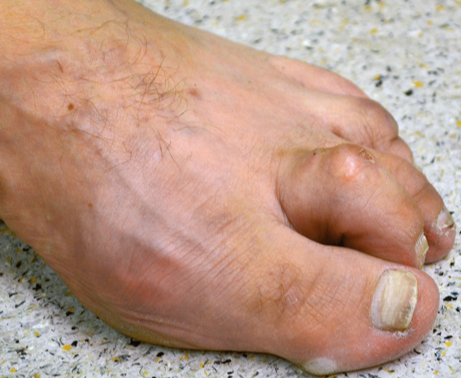

Dabei treten zu unterschiedlichen Lebensaltern verschiedene Erkrankungen auf. Neugeborene können unter anderem mit einem Klumpfuß zur Welt kommen, Schulkinder leiden häufig an Fußdeformitäten, insbesondere an Knickfüßen. Im Erwachsenenalter bereiten häufig Hühneraugen, Fehlstellungen der Großzehe wie der Hallux valgus oder Hammerzehen und Krallenzehen der Kleinzehen, erhebliche Beschwerden. Durchblutungsstörungen oder eine Zuckerkrankheit können mit zunehmendem Alter die Problematik verschärfen, es können daraus gefährliche Erkrankungen entstehen.

Krallenzehe